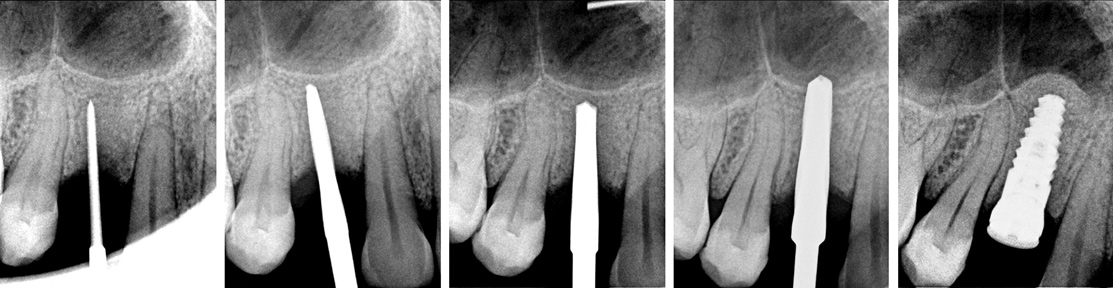

Fig 15. A series of intraoperative x-rays demonstrating sequential use of OD burs along with graft and implant placement. Note graft confinement at the apex of the implant indicating intact Schneiderian membrane.

Figure 15